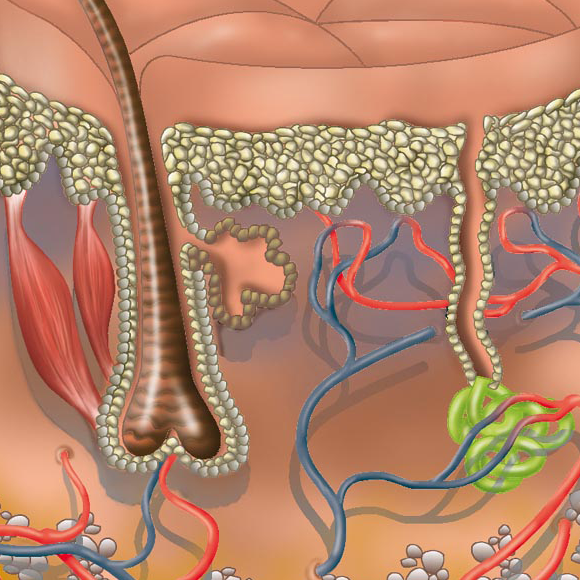

Herzlich willkommen! Ich bin Ihre Expertin für medizinische Illustrationen und kreative Kinderbuch-Illustrationen. Mit einem Auge für wissenschaftliche Genauigkeit und einer Liebe zur Gestaltung kindgerechter Erzählwelten schaffe ich Bilder, die informieren und begeistern. Entdecken Sie mein Portfolio und lassen Sie sich von meiner Arbeit überzeugen!